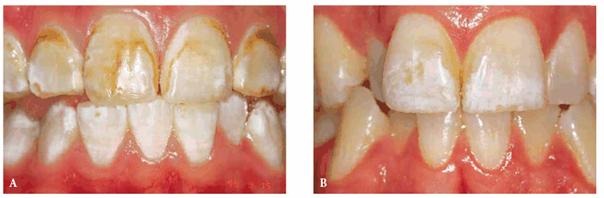

either on an individual tooth or on all teeth (Figures 16-1A, and 16-1B). There are many causes and

Figure 16-1A: An otherwise attractive smile is marred by discolored teeth.

Figure 16-1B: After tooth lightening, the smile is much more pleasing.